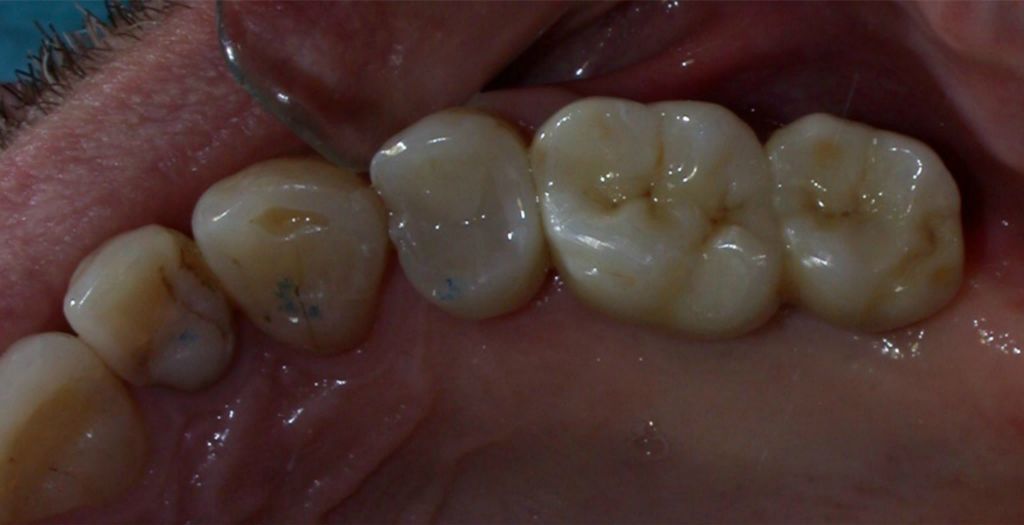

Zirconia Implants